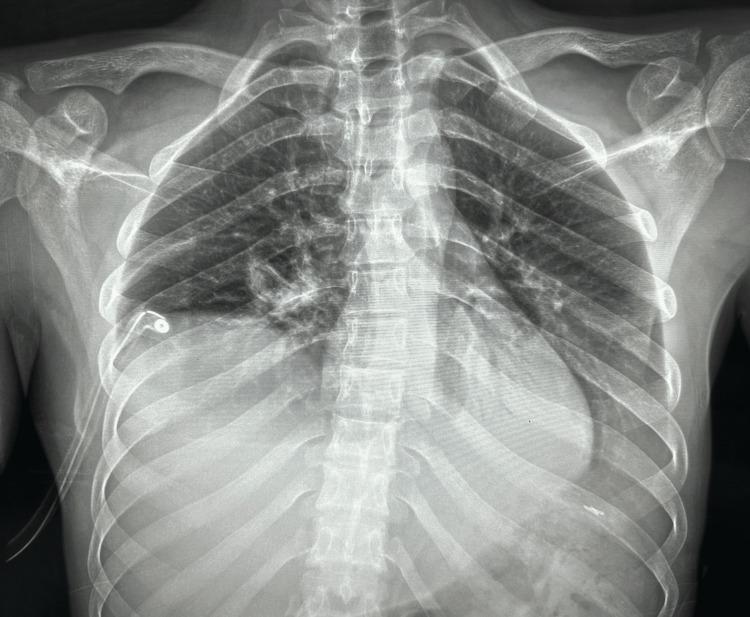

Traumatic diaphragmatic hernia (TDH) is a rare condition resulting from blunt or penetrating thoracoabdominal trauma and is characterized by the protrusion of abdominal organs into the thoracic cavity through a ruptured diaphragm. Due to its diverse clinical presentations, TDH often faces diagnostic challenges. Accurate diagnosis relies on imaging studies and surgical exploration, with surgical intervention being the primary treatment approach. This case presentation highlights a young patient who presented to Saint George Hospital following a blunt thoracoabdominal injury. The patient experienced unexplained dyspnea upon admission, and imaging revealed herniated bowels in the left hemithorax. Laparoscopic exploration confirmed a left hemi-diaphragmatic tear, with the transverse colon, omentum, most of the small bowel, and stomach herniating into the left hemithorax. The patient underwent laparoscopic repair, involving the reduction of the herniated organs into the peritoneal cavity and tension-free primary closure with gastropexy without the use of mesh for reinforcement. The patient's postoperative course was uneventful, and complete recovery was achieved. This case report provides insights into the diagnosis and management of TDH, highlighting the importance of prompt recognition and appropriate surgical intervention in achieving successful outcomes.

创伤性膈疝(TDH)是一种由钝性或穿透性胸腹外伤导致的罕见病症,其特征是腹部器官通过破裂的膈肌突入胸腔。由于其临床表现多样,TDH常常面临诊断挑战。准确诊断依赖于影像学检查和手术探查,手术干预是主要的治疗方法。本病例报告重点介绍了一名因钝性胸腹外伤就诊于圣乔治医院的年轻患者。患者入院时出现不明原因的呼吸困难,影像学检查显示左半侧胸腔内有肠管疝入。腹腔镜探查证实左侧半膈肌撕裂,横结肠、大网膜、大部分小肠和胃疝入左半侧胸腔。患者接受了腹腔镜修补术,包括将疝入的器官回纳至腹腔,并进行无张力一期缝合加胃固定术,未使用补片加强。患者术后恢复顺利,实现了完全康复。本病例报告为TDH的诊断和治疗提供了见解,强调了及时识别和适当手术干预对取得成功治疗效果的重要性。